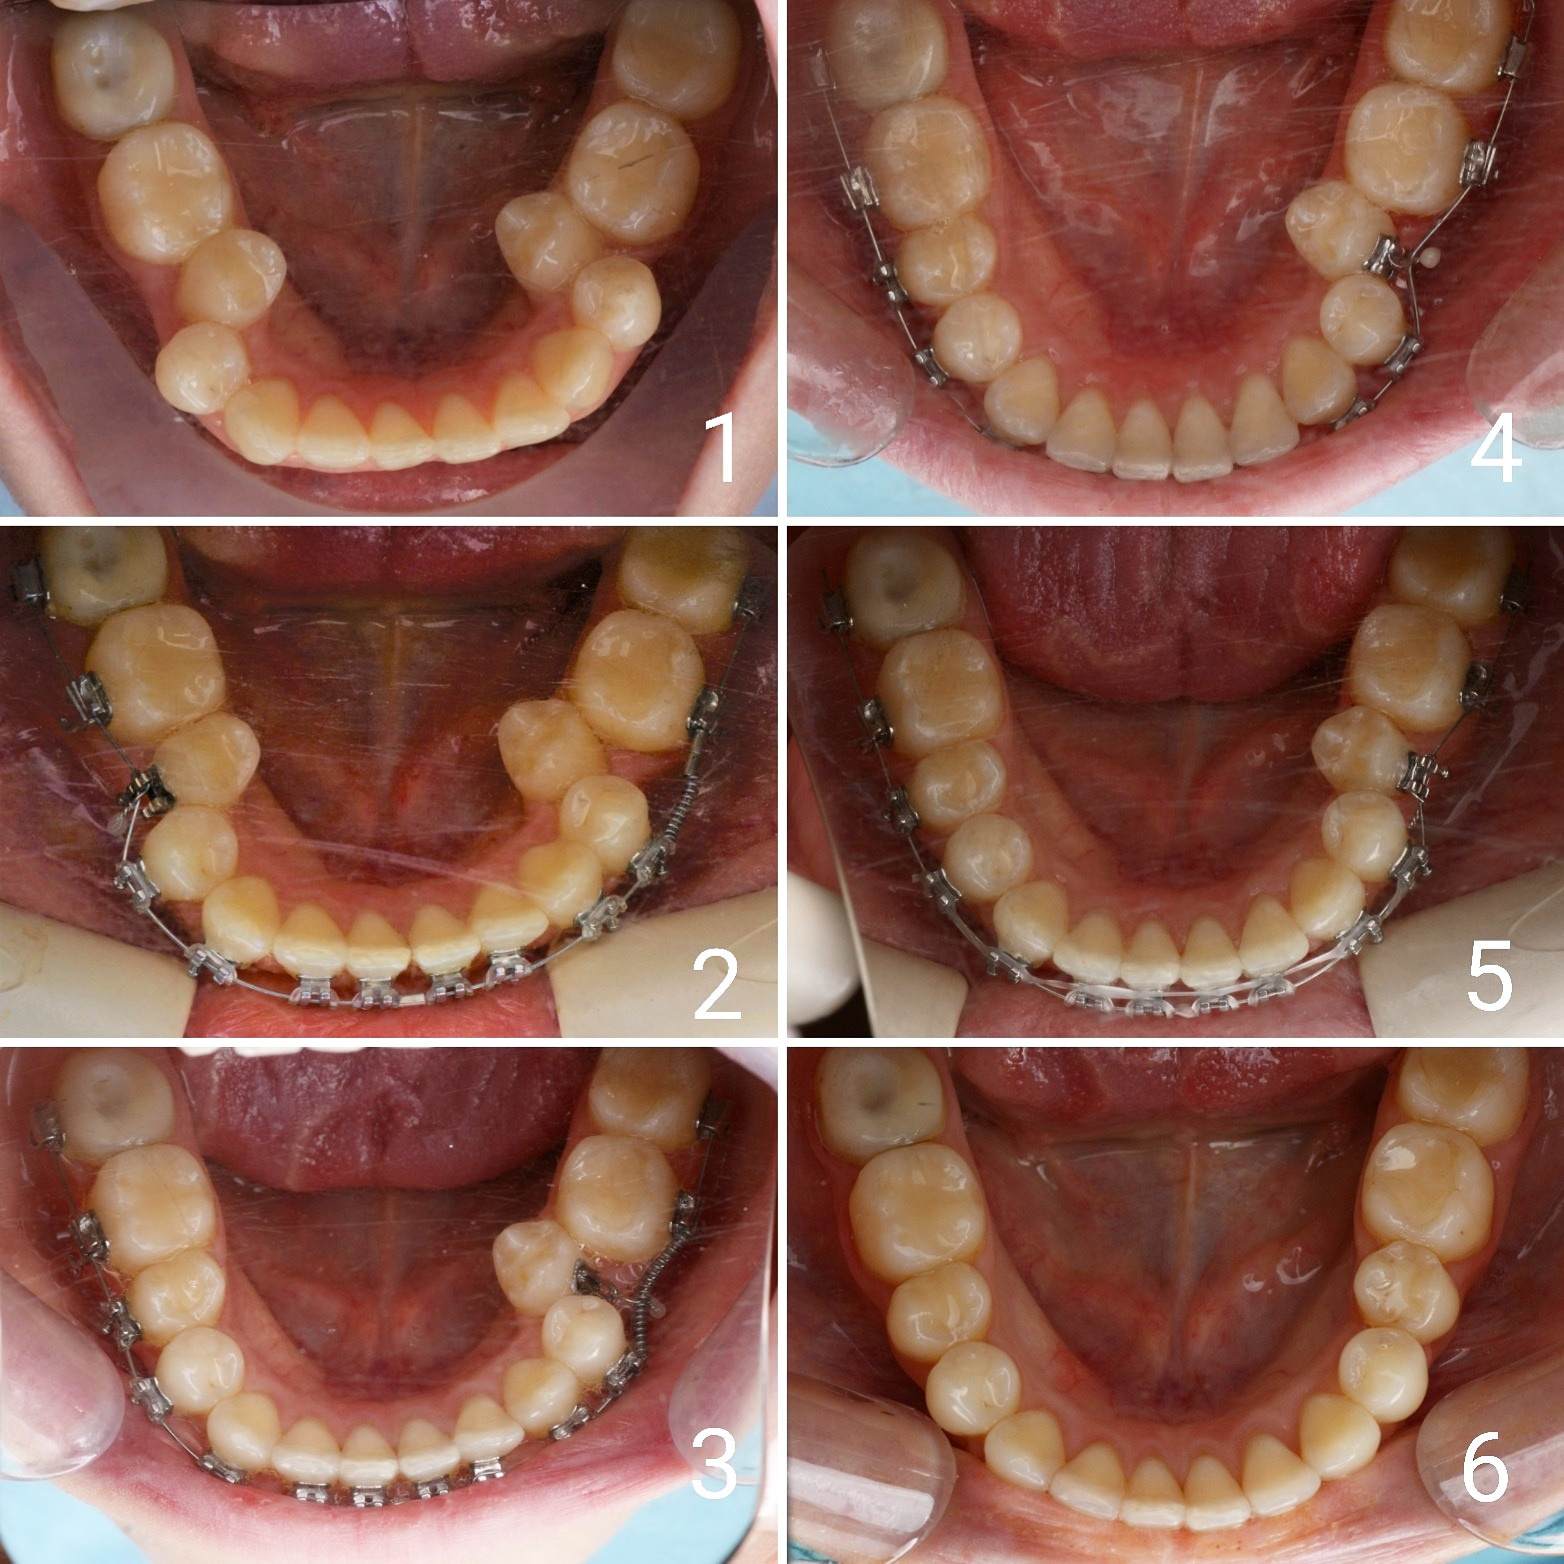

Большое путешествие зубов на своё законное место.

❗"Ждите до 12 лет, когда прорежутся постоянные зубы, тогда поставим вам брекеты". ❗

Эта фраза знакома многим ответственным родителям, которые привели на приём к ОРТОДОНТУ своего ребёнка в 5-10 лет, заподозрив проблему или понимая, что места постоянным зубам откровенно не хватает! Горькая правда в том, что брекеты - не волшебное средство от всех проблем, они "расставляют" зубы внутри сформированого объёма челюсти, но никак не влияют на её рост. Родители ждут, а тем временем драгоценное время, когда ребёнок растёт, уходит... Во взрослом возрасте приходится удалять здоровые зубы или прибегать к ортогнатической хирургической операции. 📸 На фото узкая нижняя челюсть, места постоянным зубам нет, боковые резцы прорезываются "вторым рядом".

❓Ну что? Будем ждать 12 лет? Или будем помогать ребёнку?

✅ Помогаем с помощью расширяющей дуги, пружины и зацепных элементов, которые зафиксированы на МОЛОЧНЫЕ зубы

За 3 года (после завершения ортодонтического лечения) Вадим заметно подрос и возмужал😄, а главное, его угрюмое "Я не улыбаюсь" превратилось в широкую и яркую улыбку! Как быстро растут дети!😅